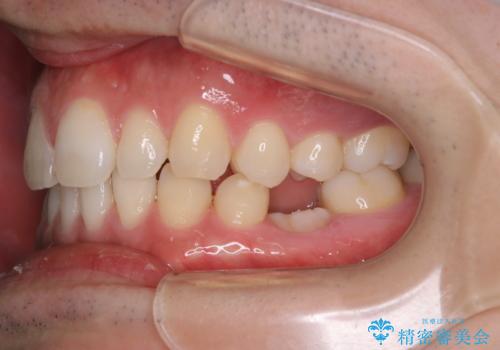

親知らずを抜いて1週間後にPMTC 歯のクリーニング

- 親知らずの抜歯後の約1週間後に抜糸(縫った部分の糸とり)で来院されました。その際、抜歯後は傷口が怖くて歯磨きが上手くできず、汚れや口臭が気になるためクリーニングも希望されました。

抜歯後は多少出血したり、違和感や痛みを感じたりすることがあります。そのため親知らずを抜いたり、外科的な処置をするといつも通りの歯磨きがしづらくなります。また、傷口の周りが心配で、歯ブラシをするのが怖くなるものです。抜歯後落ち着いたら、歯科医院にて専門の機械を使用しクリーニングをすることがおすすめです。抜歯前や後にPMTCを行うことで、お口の中の健康維持につながり、その後の感染・腫れ・口臭予防などになります。

親知らず抜歯後正常に治癒が進んでいれば1週間後から可能です。